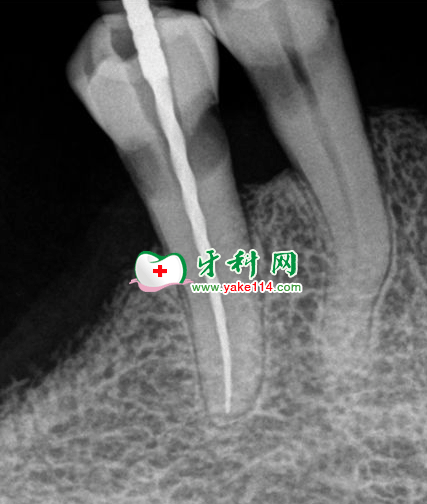

處理:0.5%聚維酮碘溶液消毒術(shù)區(qū)黏膜,4%阿替卡因腎上腺素注射液0.5ml術(shù)區(qū)黏膜下浸潤(rùn)麻醉,開髓,拔髓,測(cè)量根管(單根19.5mm)。

EDTA、0.9%氯化鈉注射液反復(fù)擴(kuò)洗至F3,隔濕,吹干,必蘭根充糊劑+牙膠尖充填,X線示恰充,磷酸鋅水門汀墊底,復(fù)合樹脂充填,常規(guī)醫(yī)囑。

根充后效果。單根牙治療比較簡(jiǎn)單,相對(duì)難度較低,對(duì)臨床操作技術(shù)的練習(xí)很有幫助。